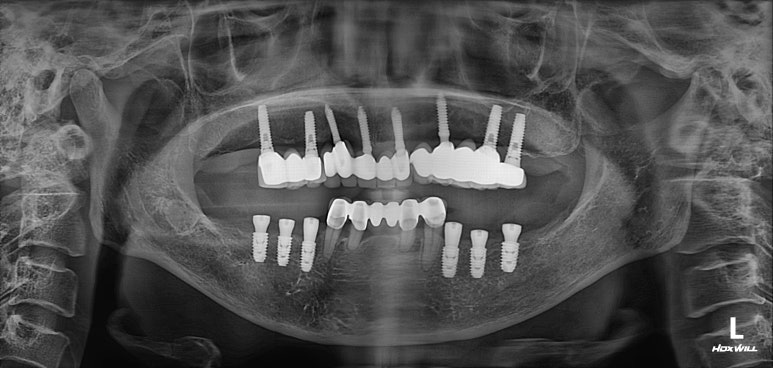

수술 후 촬영한 치과용 파노라마 사진에서, 정~말 깔끔하고 예쁘게 식립된 임플란트를 보실 수 있습니다.

아래턱뼈 내부에는 하치조신경이라는 감각신경이 주행하고 있는데요, 네비게이션 임플란트를 통해 수술 후 감각마비 없이 깔끔하게 마무리 되었습니다.

치과용 파노라마 사진을 보면 뭔가 좌우 대칭으로 깔끔하게 완성된 아래턱 양쪽 어금니 임플란트를 보실 수 있어요!!

치과용 파노라마 엑스레이만 보아도, 임플란트 여섯개가 깔끔하게 제작된 것을 보실 수 있을겁니다.